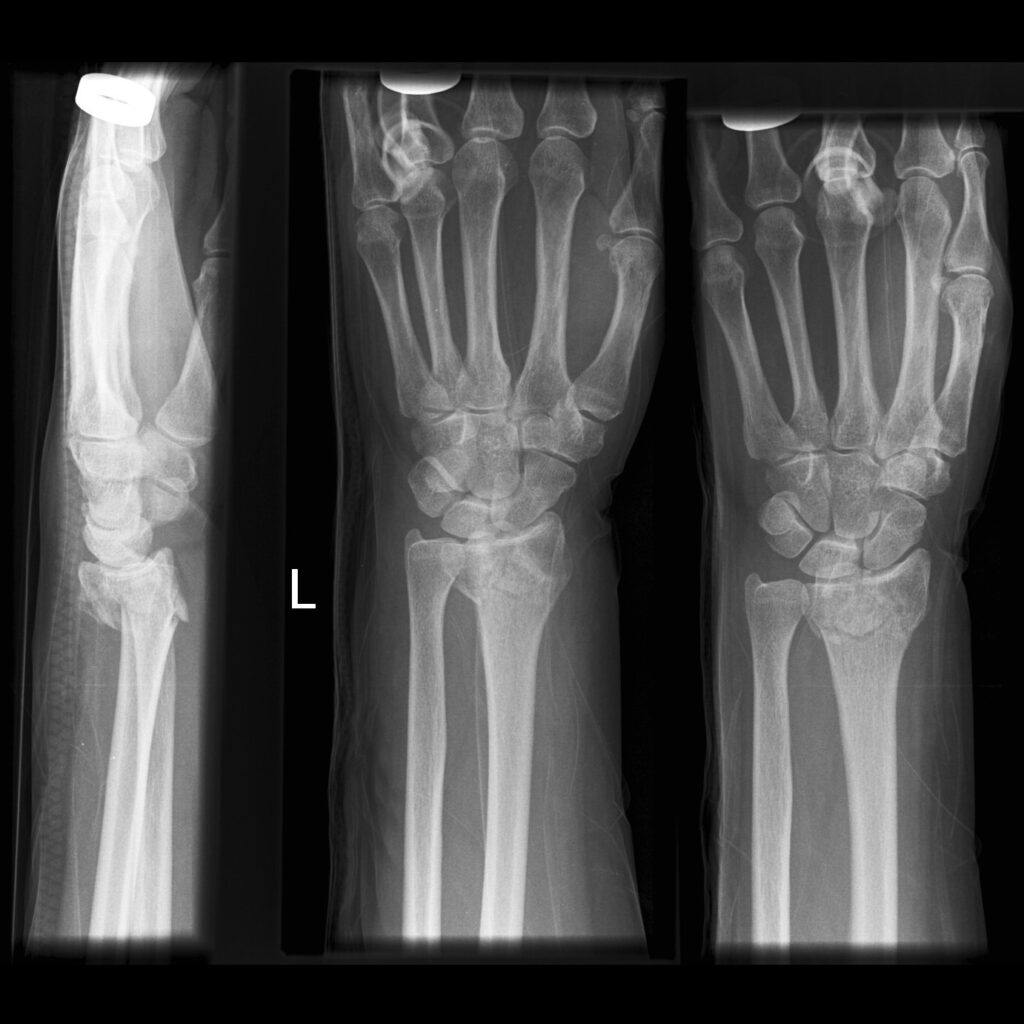

Colles' Fracture

This type of fracture is often described as being an extra-articular transverse fracture of the distal radius with dorsal displacement with/without ulnar styloid fracture. The fracture is usually around 2cm proximal to the radiocarpal joint.

1. X-Ray: AP and Later x-rays of the wrist. Oblique views of the wrist may also be beneficial. The radiological features include:

1. Dorsal tilt of the distal fragment

2. Dorsal displacement of the distal fragment

3. Ulnar styloid fracture

4. Radial shortening

5. Radial tilt

6. Radial displacement

Case courtesy of Dr MT. Niknejad, Radiopaedia.org. From the case rID: 87136